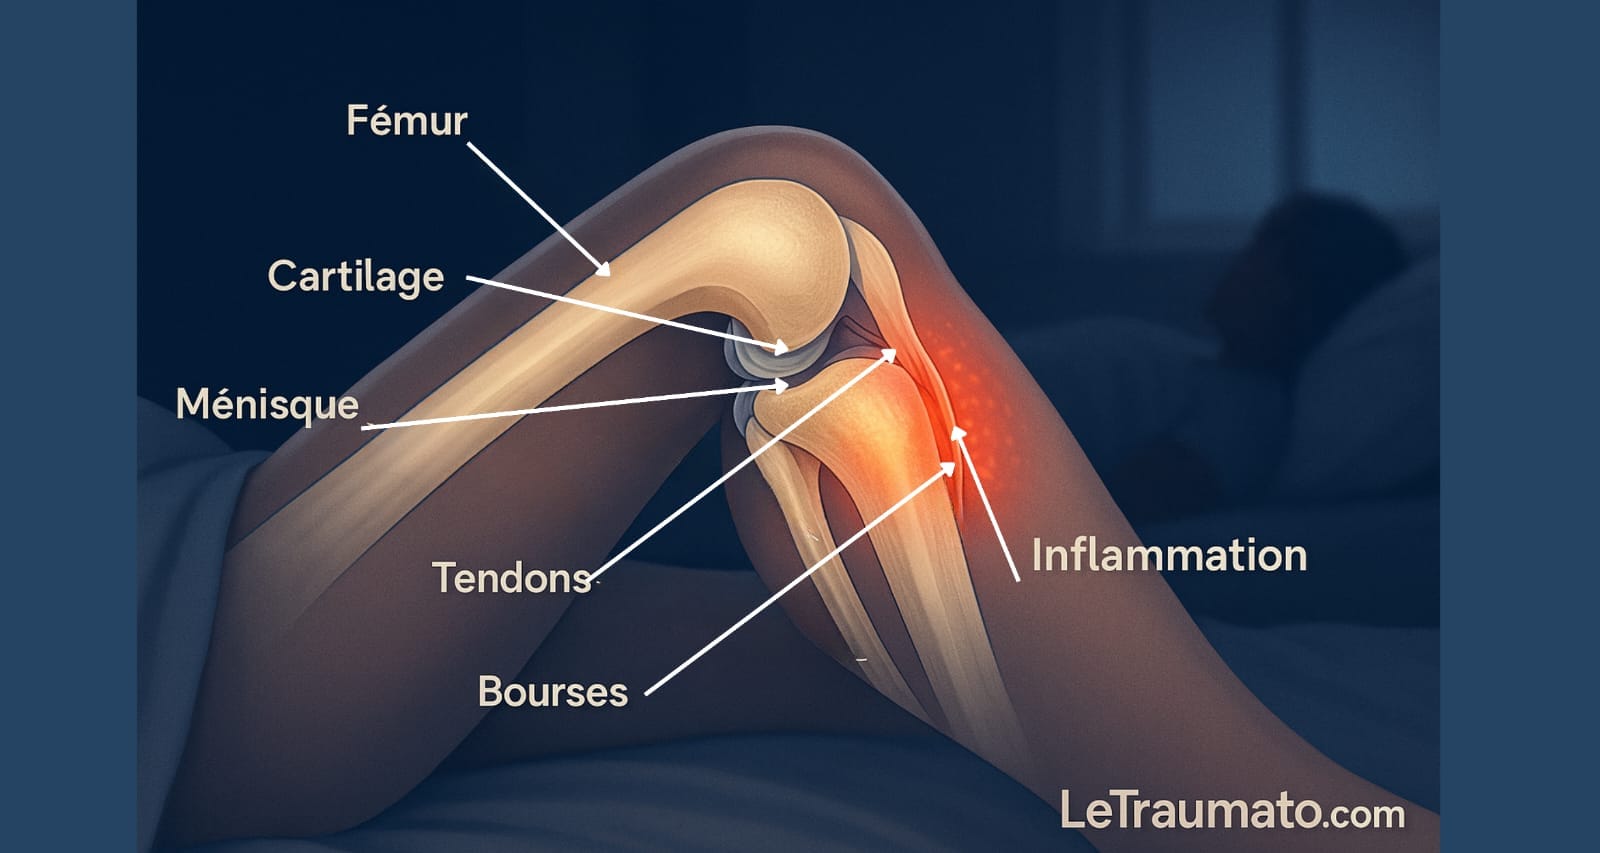

La douleur du genou en position allongée ou au repos n’est pas rare. Elle peut être le signe d’une affection articulaire chronique ou aiguë. Contrairement aux douleurs liées à l’effort, les douleurs nocturnes sont souvent inflammatoires ou mécaniques.

Les mécanismes de l’inflammation au repos

Lorsque le corps est au repos, l’inflammation peut se manifester plus intensément. Le ralentissement du métabolisme et la baisse des hormones anti-inflammatoires pendant la nuit augmentent la sensibilité à la douleur. Le liquide synovial peut s’accumuler, provoquant une sensation de pression et de raideur.

L’arthrose est la cause la plus fréquente. Elle touche 30 à 40 % des plus de 60 ans. La dégradation du cartilage provoque un frottement des os entre eux, surtout perceptible à froid, c’est-à-dire la nuit ou au réveil.

Tendinite et bursite du genou

Les tendinites sont fréquentes chez les sportifs ou les personnes en surpoids. Elles peuvent devenir chroniques et douloureuses la nuit. Quant aux bursites (inflammation des bourses séreuses), elles génèrent des douleurs localisées et pulsatiles, même au repos.

Lésions méniscales ou ligamentaires non traitées

Une lésion du ménisque, même ancienne, peut se réveiller en position allongée. Le genou devient douloureux lors d’un mouvement involontaire la nuit. Les douleurs ligamentaires post-traumatiques sont aussi fréquentes après une entorse mal soignée.

Infections articulaires ou pathologies inflammatoires

Certaines douleurs nocturnes peuvent révéler une infection (arthrite septique) ou une maladie inflammatoire (polyarthrite rhumatoïde, goutte). Ces douleurs s’accompagnent souvent de rougeur, chaleur locale et fièvre.